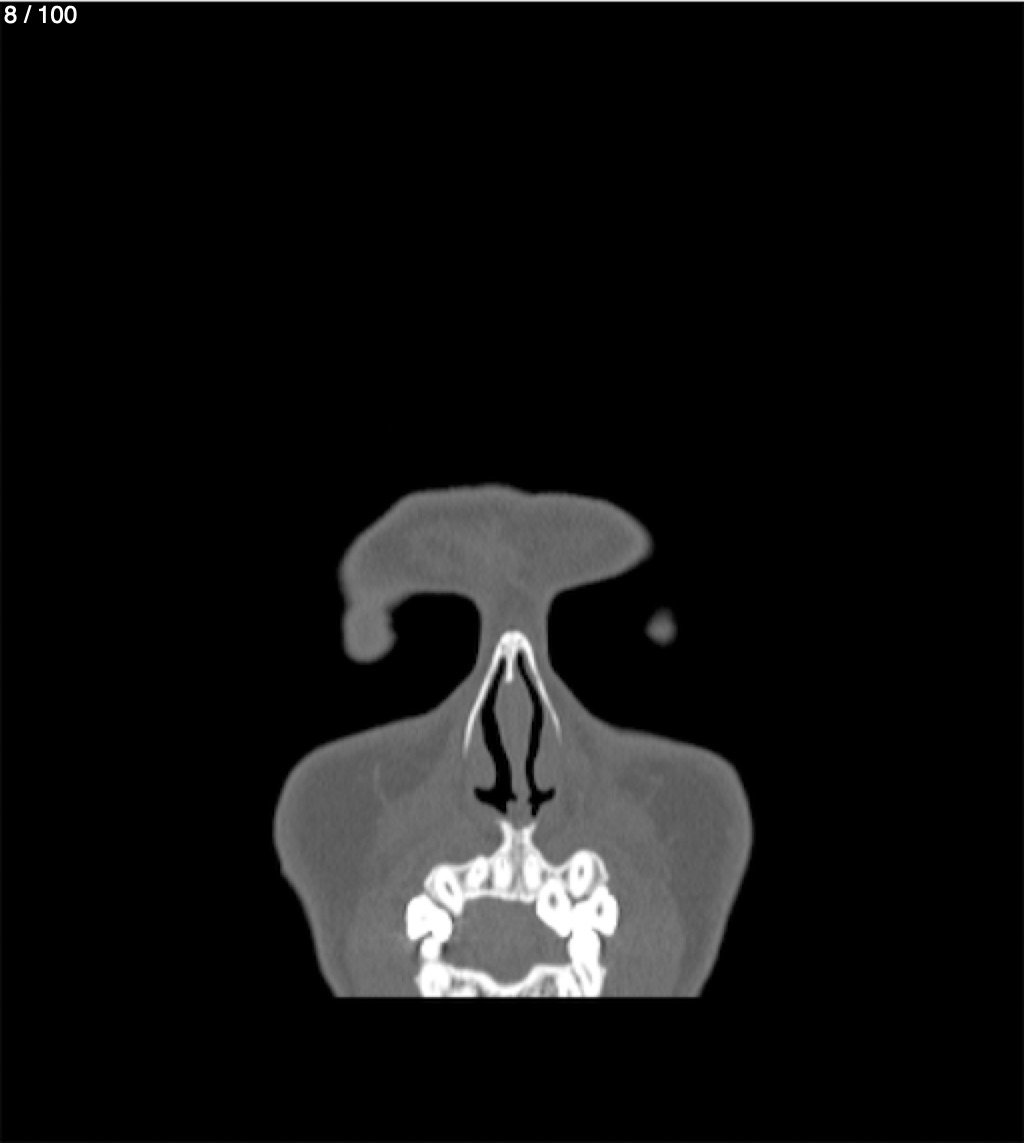

Yonelly Barrios Diaz 35A - T.C Craneo